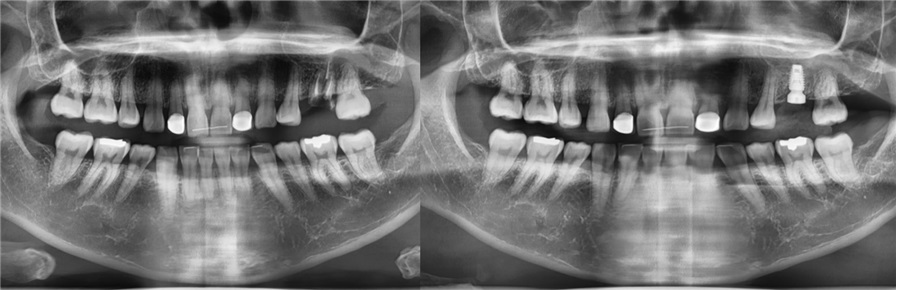

치료전후사진